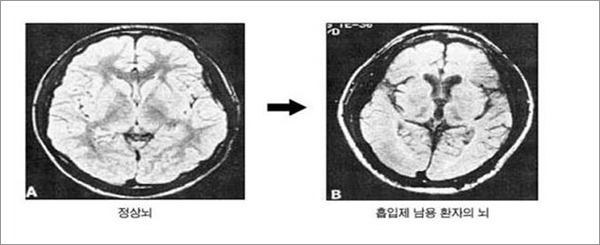

본드랑 가스 빨면 뇌 이렇게 된다는디

뇌 쭈글 ~ 쪼글